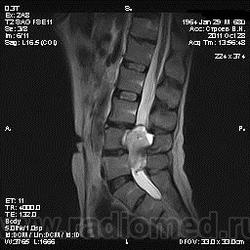

Жалобы на боли в пояснице постоянного характера, исследование началось после приема обезболивающего препарата, предоставлены выписки после неоднократного лечения в стационаре с диагнозом: Полисегментарный остеохондроз, деформирующий спондилез, грыжа диска L4-5, протрузия диска L3-4, умеренно выраженный болевой синдром.

От оперативного лечения отказался по поводу эпиприступов в анамнезе.

По структуре и локализации образование, вероятно, исходящее из корешков спинного мозга. Как у него с тазовыми функциями?

То что видно -слишком гомогенный сигнал для дермоида. Учитывая деформацию костных структур- заболевание существует давно. И не забыть внимательно посмотреть на предмет spina bifida, может это вообще грыжа. Контрастику бы налить.

я за невриному , структура гомогенная , а дермоид , неоднороден и выглядит как "губка", то есть с мелкими очагами повышенного мр-сигнала в Т2. по- моему...

вообще то забираю свои слова обратно (не согласна с невриномой) ... одолели сомнения.. там кажется есть кистозный компонент , отличный от сигнала спинномозговой жидкости . гистология покажет ))

Кистозный компонент не исключает невриному.

в литературе говорится что экскавация или продавливание задней поверхности позвонка- тоже характерная черта роста неврином в этой локализации.